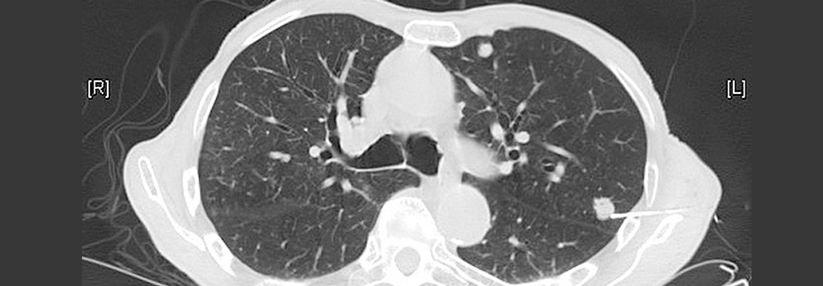

Tochtergeschwülste bilden sich beim NSCLC vor allem in der kontralateralen Lungenhälfte, dem Gehirn und den Nebennieren aus. Tochtergeschwülste bilden sich beim NSCLC vor allem in der kontralateralen Lungenhälfte, dem Gehirn und den Nebennieren aus. © iStock/Mohammed Haneefa Nizamudeen

In den Untersuchungen lagen die Tochtergeschwülste vor allem in der kontralateralen Lungenhälfte, dem Gehirn und den Nebennieren. Verschiedene lokale Ablationsverfahren kamen zum Einsatz, meist die chirurgische Resektion. Patienten mit metachron auftretenden Metastasen schnitten im Mittel besser ab als Patienten mit synchroner Filialisierung. Daten gibt es vor allem zur bilateralen chirurgischen Resektion von Primärtumor und kontralateralen Metastasen. Das 5-Jahres-Überleben lag zwischen 30 % und 50 %. Auch mit einer ablativen Radiotherapie hat man bei pulmonalen Metastasen gute Kontrollraten von etwa 90 % nach zwei Jahren erzielt. Für inoperable Patienten eignet sich eine stereotaktische Bestrahlung. Sie lässt sich leicht repetitiv anwenden, auch an anatomisch schwierigen Stellen. Doch die chirurgische Resektion bietet den Vorteil, dass sich Histologie und Resektionsränder beurteilen lassen. Im Langzeit-Outcome scheint sie überlegen.  Bis zu ein Drittel der NSCLC-Patienten hat zum Zeitpunkt der Diagnose synchrone Hirnfiliae. Jahrzehntelang erfolgte deren Behandlung mittels Ganzhirnbestrahlung, meist ergänzend zu einer Operation. Die chronischen neurologischen Nebenwirkungen dieser Radiatio waren jedoch erheblich. Standardverfahren in der Therapie isolierter Herde – ein bis drei - ist heute die stereotaktische Radiochir­urgie (SRS). Damit lässt sich eine vergleichbar gute lokale Kontrolle erreichen wie mit postoperativer Ganzhirnbestrahlung.  Etwa 5 % der Kranken mit operablem NSCLC weisen bei Diagnosestellung einzelne Nebennierenmetastasen auf, die für eine ablative Therapie infrage kommen. Die Adrenalektomie verlängert das Überleben, in Studien ermittelte man für ausgewählte Patienten 5-Jahres-Überlebensraten > 25 %. Alternativ bietet sich für Menschen in schlechtem Allgemeinzustand eine stereotaktische Bestrahlung  an, die in mehr als 80 % der Fälle eine gute lokale Kontrolle erzielt.  Entscheidend für den Erfolg all dieser Ansätze ist die Selektion geeigneter Kandidaten mit günstiger Prognose. Für körperlich fitte Kranke empfehlen die Autoren ein strategisches Vorgehen (s. Kasten). Die besten Ergebnisse sind zu erwarten bei Patienten ohne N2-Lymphknotenbefall und mit weniger als vier metachronen Organmetastasen.